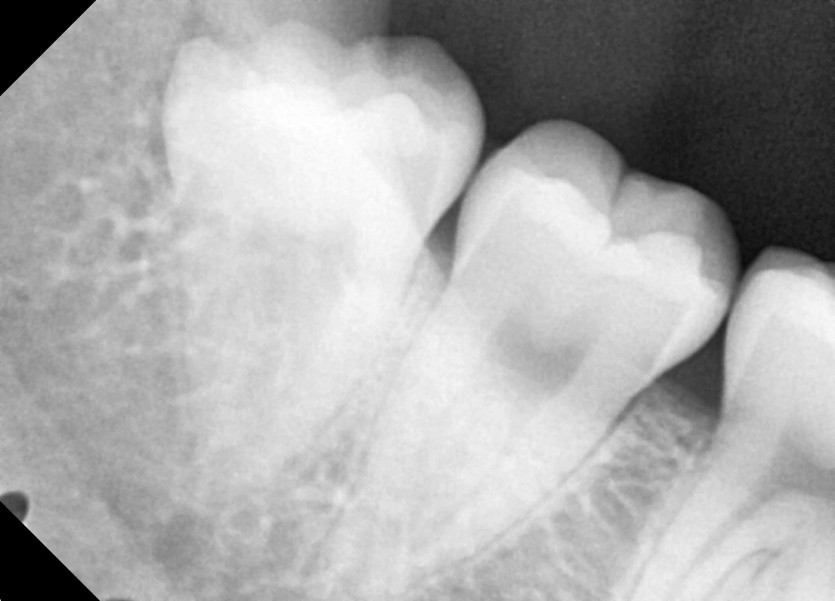

#18,28,38,48 사랑니 발치

구강 외과 전문의가 당일 발치했습니다.